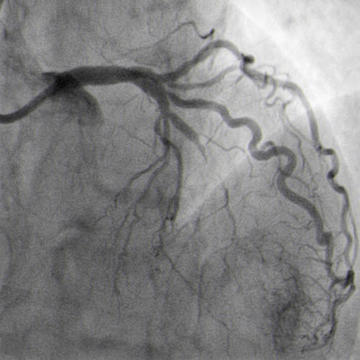

Final result with TIMI III flow, no leak (Figure 10)

Implantation of the covered stent (Figure 9).

Covered stent implanted (Figure 9)